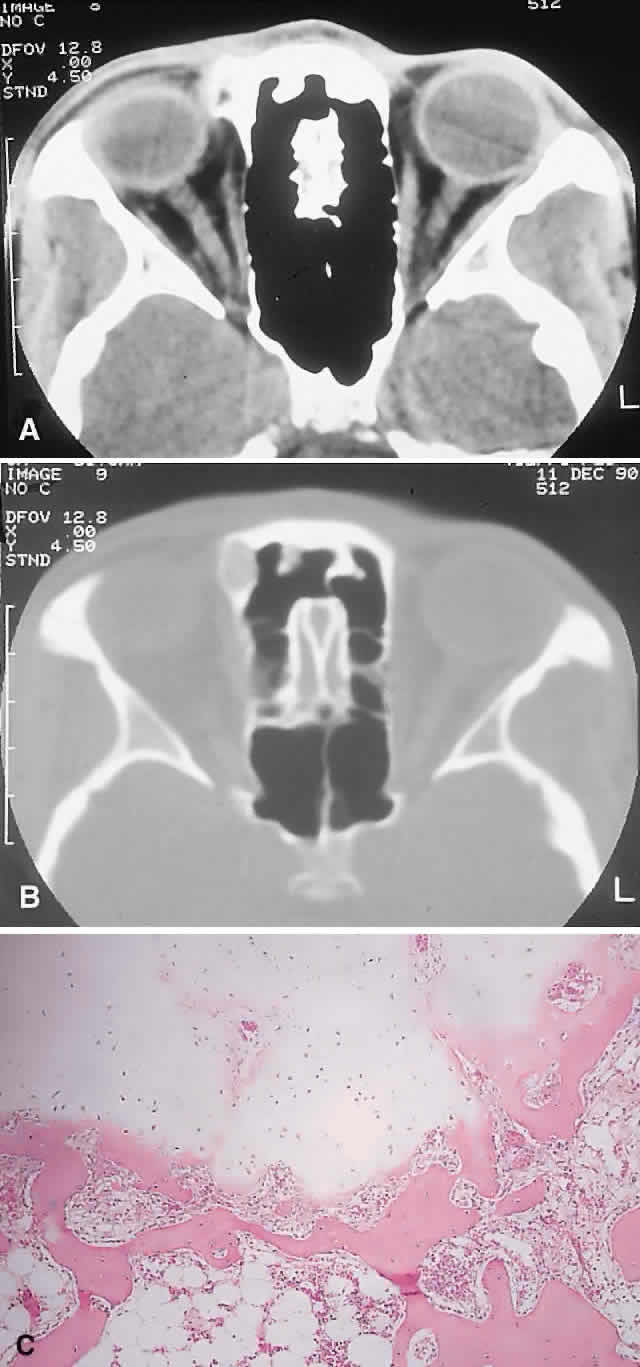

PRESENTATION. Most sinus osteomas are solitary and asymptomatic.6 However, when large enough to encroach on the orbits, a gradual evolution of proptosis or globe displacement over many years can occur (Fig. 1). There may be an associated headache as a result of expansion of the overlying cortex and periosteum, and a bony mass is often palpable in the superior or superomedial orbit. Obstruction of the sinus ostia may lead to chronic sinusitis or mucocele. Less common features include an acquired Brown syndrome,10 gaze-evoked amaurosis or pain,4,11 subluxation of the eye12 and erosion leading to orbital emphysema, or cerebrospinal fluid rhinorrhea.13 The sphenoid sinus, although a rare site, is significant because even a small lesion may lead to an orbital apex syndrome.

Fig. 1. A. A 15-year-old boy with a 10-month history of left proptosis had an inferolaterally displaced globe and 6 mm of proptosis. B. CT scan showed a circumscribed sclerotic mass arising from the frontoethmoidal area, with a frontal mucocele laterally. C. Bone windows revealed the bony mass to have a cancellous core and a sclerotic periphery. D. The histology showed a peripheral zone of compact bone, with increasing osteoblastic activity and fibrous tissue toward the center (hematoxylin-eosin, × 5). E and F. Higher power revealed areas of compact bone with haversian canals similar to normal cortical bone and regions of trabecular bone (F) with more osteoblastic activity present (hematoxylin-eosin, × 20).

IMAGING. The plain radiograph and CT appearances consist of an osteoblastic round or ovoid sharply circumscribed mass, usually arising in the sinus and invading the orbit. Tumors growing in a sinus conform to its internal contour and often have a bosselated surface. Osteomas may be sessile or pedunculated and generally have a diameter of 1 to 5 cm.18 Bone window settings on CT imaging often show a very dense periphery with a more cancellous internal structure. However, the relative proportions of the two densities may vary with the size of the lesion.

The compact areas resemble normal cortical bone with dense bony areas and haversian systems. However, there are subtle differences in the arrangement of the haversian canals, which is often evident to the experienced bone pathologist. The cancellous areas consist of anastomosing trabeculae with an intervening fibrovascular stroma. Fatty and hematopoietic elements may also be present in the stroma, as well as evidence of osteoblastic activity along the trabeculae. The fibrous region is made up primarily of loose fibrovascular tissue with a few irregular bony trabeculae and osteoid elements.

In our series of nine surgically treated cases, we noted that although the three types of tissue were present in varying admixtures, in all cases there was a remarkably consistent pattern of arrangement. The most peripheral zone was made up of compact bone; moving toward the center or base of the lesion, there was an intermediate zone of increased osteoblastic activity, osteoid, and vascularity. The innermost region consisted of a loose fibrous stroma with a greater number of blood vessels, few trabeculae, and many plump osteoblasts. This configuration has been described previously by Albert and associates20 and illustrates the growth of these lesions.